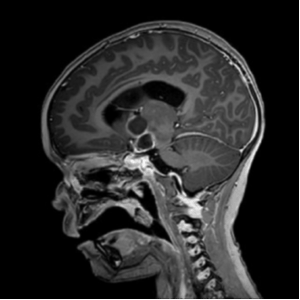

Figure 1 – MRI scan showing suprasellar craniopharyngioma. Reproduced with parental permission (2025)

The child’s presentation and MRI findings are highly consistent with a suprasellar craniopharyngioma, a locally aggressive tumour arising from remnants of Rathke’s pouch.